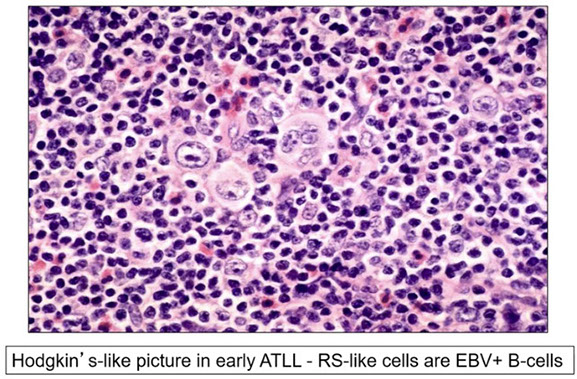

Adult T-cell leukemia / lymphoma (ATCL/ATLL)

Classic Hodgkin Lymphoma (cHL)

- Mixed-cellularity classic Hodgkin lymphoma